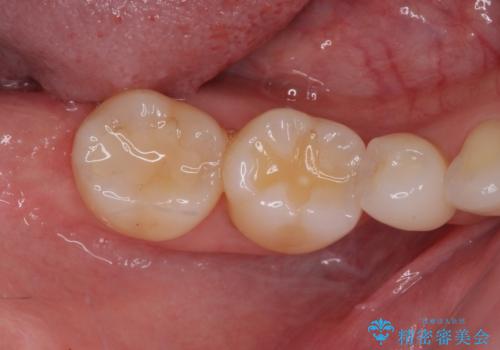

- 全体的なデコボコと、奥歯の欠損を放置した結果倒れ込んだ奥歯などを気にして来院された患者様です。

ワイヤー矯正の方が理想的な仕上がりとできる状態でしたが、上顎前歯にクラウンが装着されているため、インビザラインにて矯正治療を行うこととしました。

インビザラインのみで対応できないときにはワイヤー矯正を併用することとし、矯正治療後にはオールセラミッククラウンによる補綴治療を行うこととしました。

欠損部位は傾斜歯軸を起き上がらせることができたため、オールセラミッククブリッジにて補綴治療を行いました。